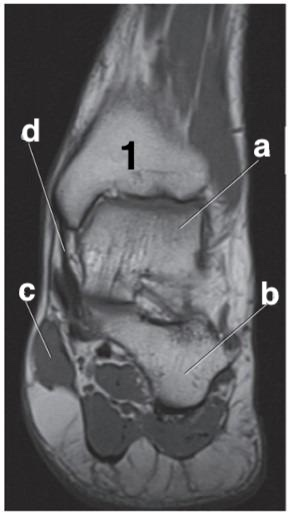

Medial meniscus

What is letter e?

posterior cruciate ligament

Which letter is pointing to the posterior cruciate ligament?

e

Which letter is the talus?

c

Achilles tendon

Which letter is pointing to the anterior cruciate ligament?